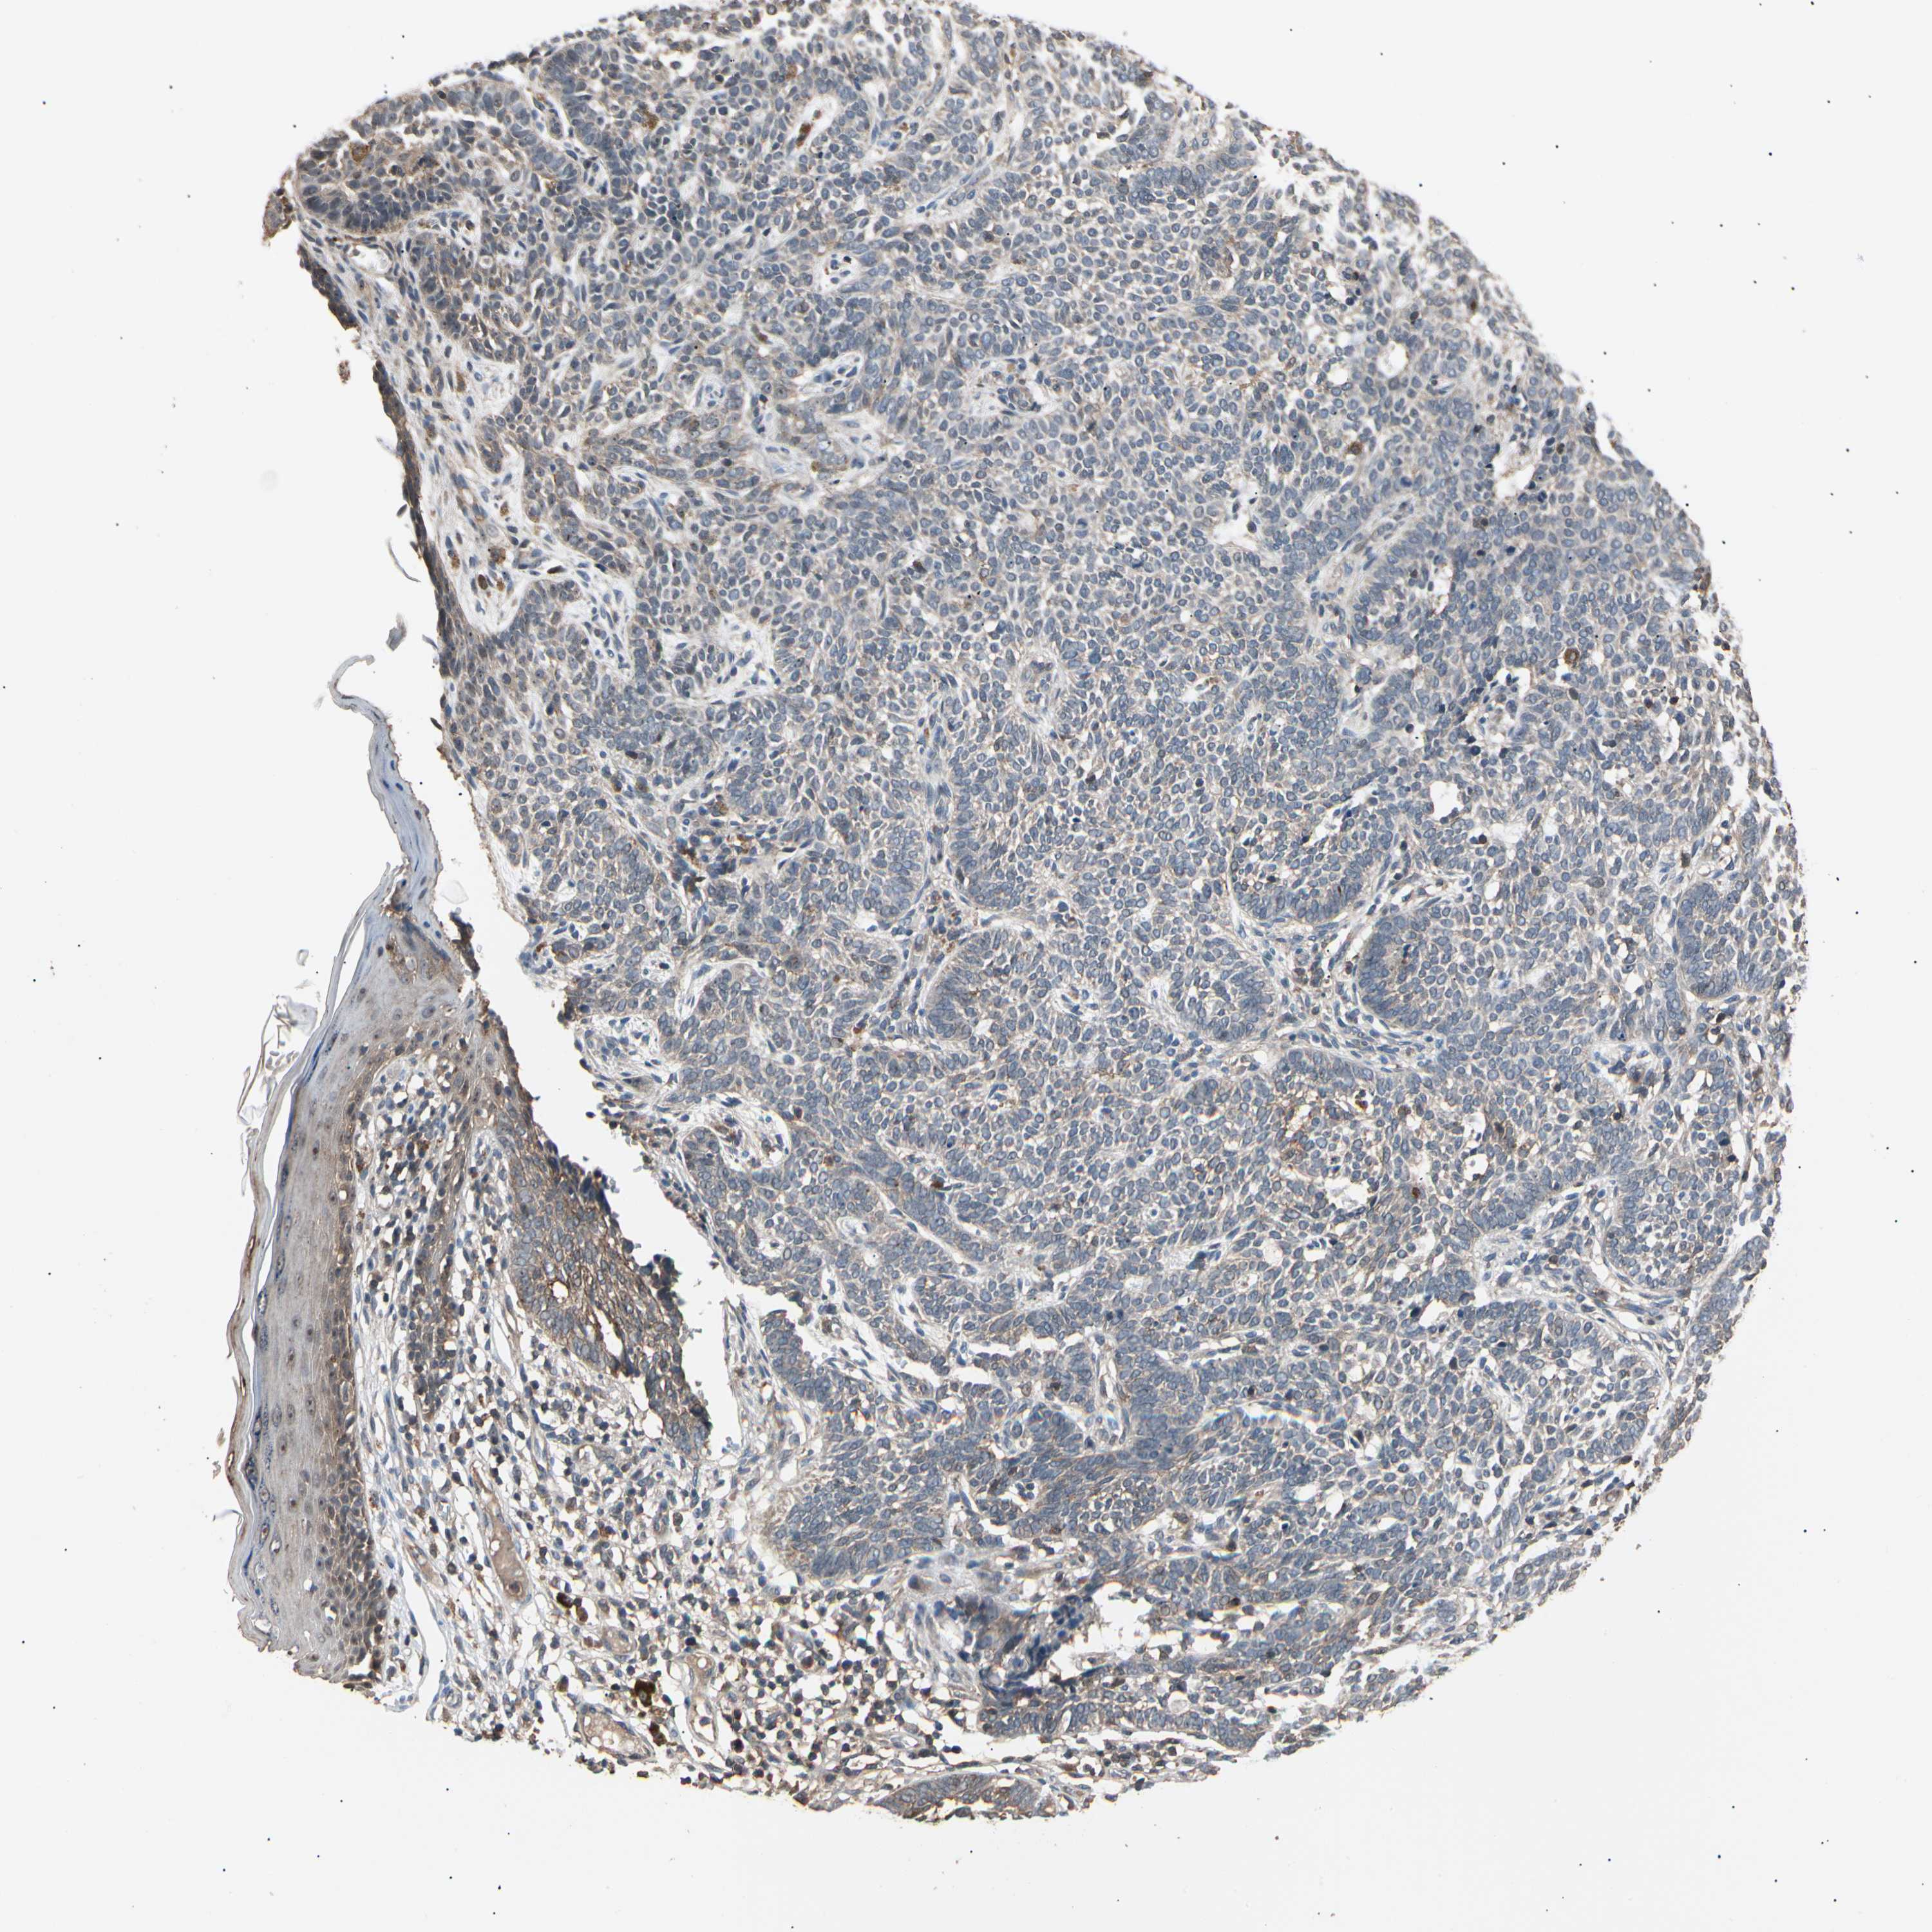

SKIN CANCER - Protein expressioni

A mouse-over function shows sample information and annotation data. Click on an image to view it in a full screen mode. Samples can be filtered based on level of antibody staining by selecting one or several of the following categories: high, medium, low and not detected. The assay and annotation is described here.

Antibody stainingi

Antibody staining in the annotated cell types in the current human tissue is reported as not detected, low, medium, or high, based on conventional immunohistochemistry profiling in selected tissues. This score is based on the combination of the staining intensity and fraction of stained cells.

Each image is clickable and will lead to virtual microscopy that enables deeper exploration of all samples and also displays staining intensity scores, fraction scores and subcellular localization as well as patient and tissue information for each sample.

Antibody HPA007667

Staining

High

Medium

Low

Not detected

Intensity

Strong

Moderate

Weak

Negative

Quantity

>75%

75%-25%

<25%

None

Location

Nuclear

Cytoplasmic/membranous

Cytoplasmic/membranous,nuclear

Squamous cell carcinoma, NOS